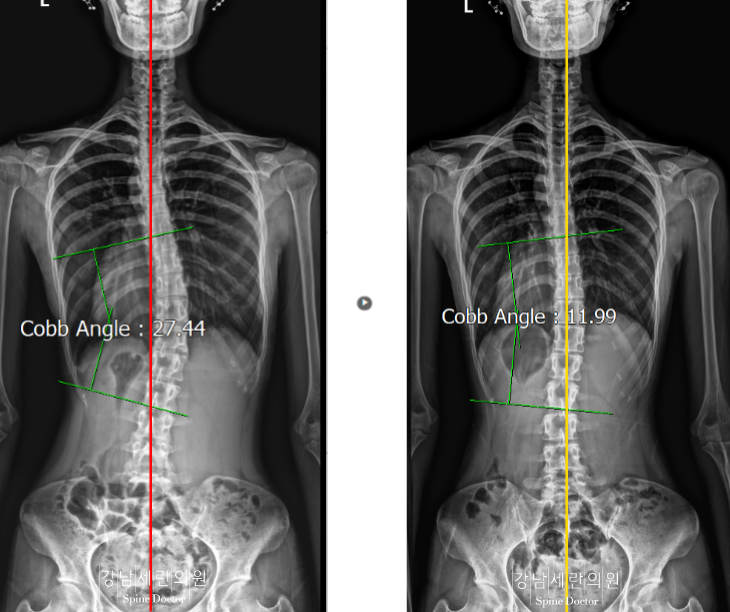

#측만증

측만증 교정 전 ▶ 측만증 20회(두 달반)교정 후 -개인 별 결과 상이

교정(20회 두 달 반) 전후-개인 별 결과 상이